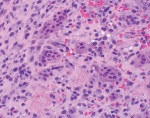

An excisional biopsy of the lesion was performed, and the specimen was submitted to a pathology laboratory. The results of the histologic analysis are shown in Figure 3 and Figure 4.

Routine microscopic analysis of PGCG reveals the presence of an abundance of multinucleated giant cells with ulcerated granulation tissue, which is a distinctive feature of PGCG (Figure 4).1 Evidence of fusion of blood monocytes forming osteoclastic multinucleated giant cells is also characteristic of PGCG (Figure 4 and Figure 5), consistent with profuse hemorrhage observed within the mass. Additionally, the presence of brown pigmentation within the histologic specimen correlates with the presence of hemosiderin and is a hallmark feature of PGCG (Figure 5).1